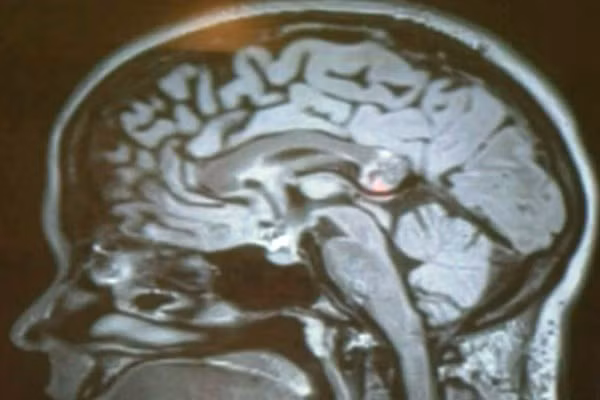

Vài tháng trước, cô Karanam đã phải đến bệnh viện điều trị vì gặp khó khăn trong việc đọc sách và giao tiếp. Cô được chuyển đến khoa nội soi Viện Skull Base ở Los Angeles. Tại đây, bác sĩ phẫu thuật Hrayr Shahinian đã phát hiện ra khối u kì lạ của cô.

Lúc đầu, các bác sỹ chẩn đoán vấn đề của cô Karanam giống triệu chứng bị u não. Tuy nhiên, trong khi phẫu thuật họ phát hiện rằng đây không phải là một khối u bình thường mà là một khối u quái Teratoma [1].

Bác sĩ Hrayr Shahinian đã rất sốc vì phát hiện ra phôi thai với đầy đủ răng, tóc và xương khi đưa một camera nhỏ xíu vào trong não của cô Karanam.